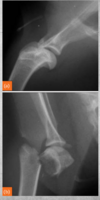

Describe the elbow joint on radiography.

Mediolaterally imaged the following can be seen: - Congruency of joint surfaces - Coronoid process - Osteophytes Craniocaudal/anterior-posteriorly the following can be imaged: - Osteophytes - Defects of humeral medial condyle - Luxation/subluxation

53

elbow mediolateral in flexion, you can spot what 3 pathologies:

- ununited anconeal process - osteophytes - flexor enthesopathy